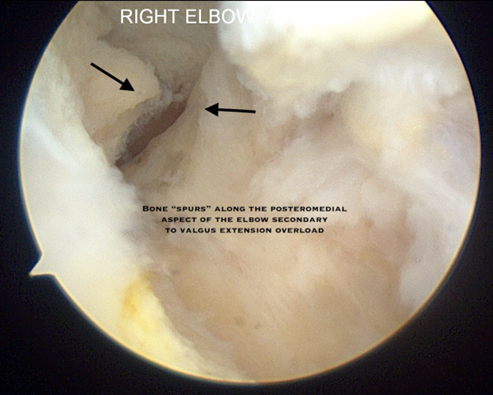

- Posteromedial osteophytes with loose bodies

- Radiographs frequently demonstrate osteophyte formation in the posteromedial olecranon

- Arthroscopic resection of osteophytes and removal of loose bodies is indicated for throwing athletes who have failed to improve or have ongoing mechanical symptoms

- Care must be taken to only remove posteromedial osteophytes and avoid over-resection as this can lead to increased stress on the ulnar collateral ligament resulting in valgus instability